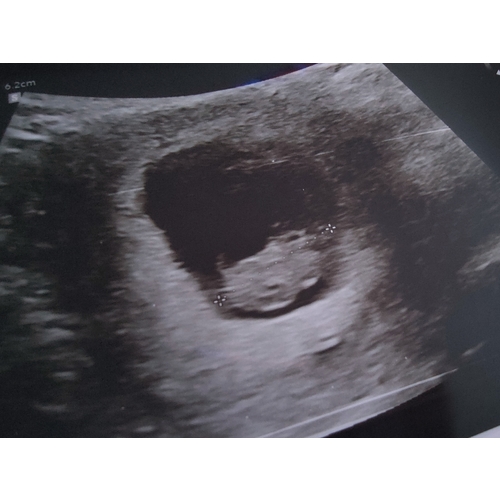

Ik dacht 8 weken te zijn bij de echo ze hadden me alleen iets terug gezet naar 7+4. Nu alweer een goede termijn echo gehad en vandaag alweer 11+4.